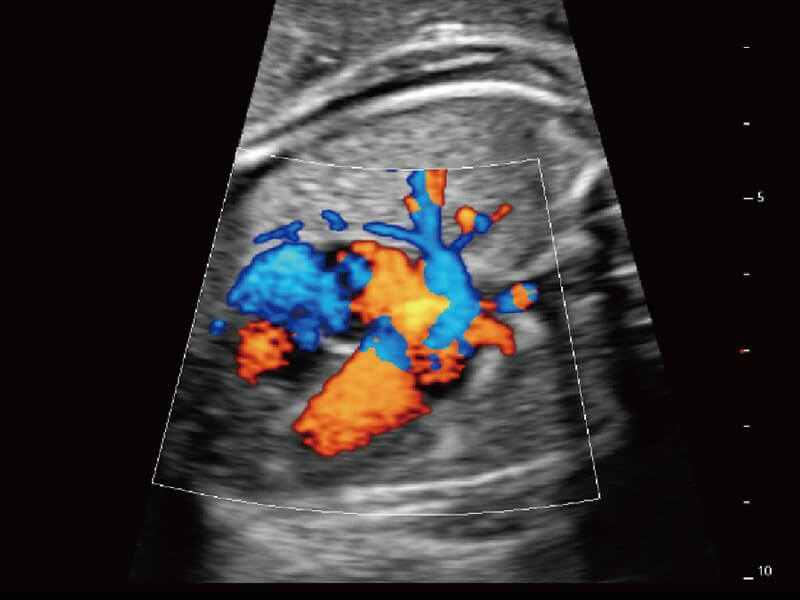

超宽频带技术,为容积成像带来优质的二维图像基础,为您呈现丰富的结构细节,栩栩如生地展示宝宝的宫内形态以及各种组织的立体结构。